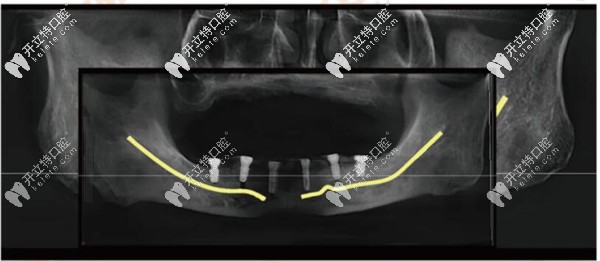

專長:全口種植即刻負重、骨增量技術、糖尿病 / 高血壓患者種植。

實例:完成 8000 + 例種植手術,曾為牙槽骨高度不足 3mm 的患者成功植入 4 顆植體全口功能。